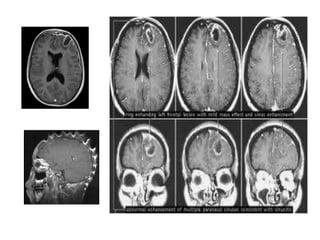

La introducción de la TAC y la RNM ha revolucionado el

En la TAC es el de una lesión hipodensa rodeada de un anillo

• La RNM parece más sensible que la TAC en la fase de cerebritis, así

DIAGNÓSTICO

En la TAC sin contraste, el empiema suele manifestarse como

La RNM proporciona mejores datos que la TAC en relación con la

sensibilidad de esta técnica.